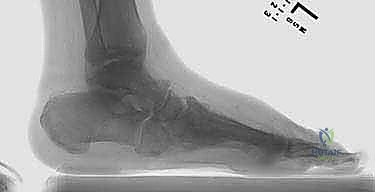

- الانهيار الهيكلي: تنهار عظام منتصف القدم، مما يؤدي إلى سقوط قوس القدم الطبيعي وتحول أسفل القدم إلى شكل محدب يشبه "الكرسي الهزاز" (Rocker-bottom deformity).

الخطوة الثانية: موازنة الأنسجة الرخوة وتطويل الأوتار

في كثير من الأحيان، يكون وتر أخيل (Achilles Tendon) مشدوداً جداً، مما يسحب الكاحل للأسفل ويزيد الضغط على منتصف القدم. يقوم الدكتور هطيف بإجراء تطويل لوتر أخيل (TAL) لتقليل الضغط الميكانيكي على مقدمة ومنتصف القدم.